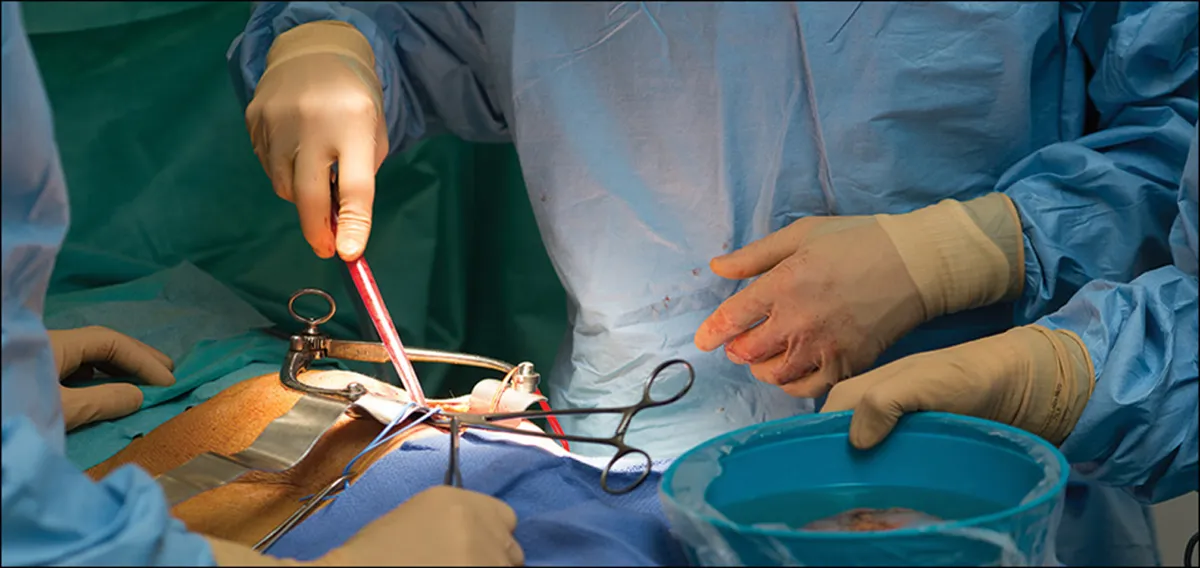

A DRPAD não é contraindicação à DP — e, na prática, muitos pacientes têm resultados comparáveis à hemodiálise. O “porém” está na mecânica: rins/hepatomegalia podem reduzir tolerância a volumes, aumentar risco de hérnias e extravasamentos, e piorar desconforto respiratório. Com técnica adequada (cateter presternal ou lateral, volumes menores, cicladora noturna e decúbito supino), a maioria das barreiras é contornável. Neste post, revisamos quando a DP é ótima, quando exigir cautela e como ajustar a prescrição para segurança e qualidade de vida.